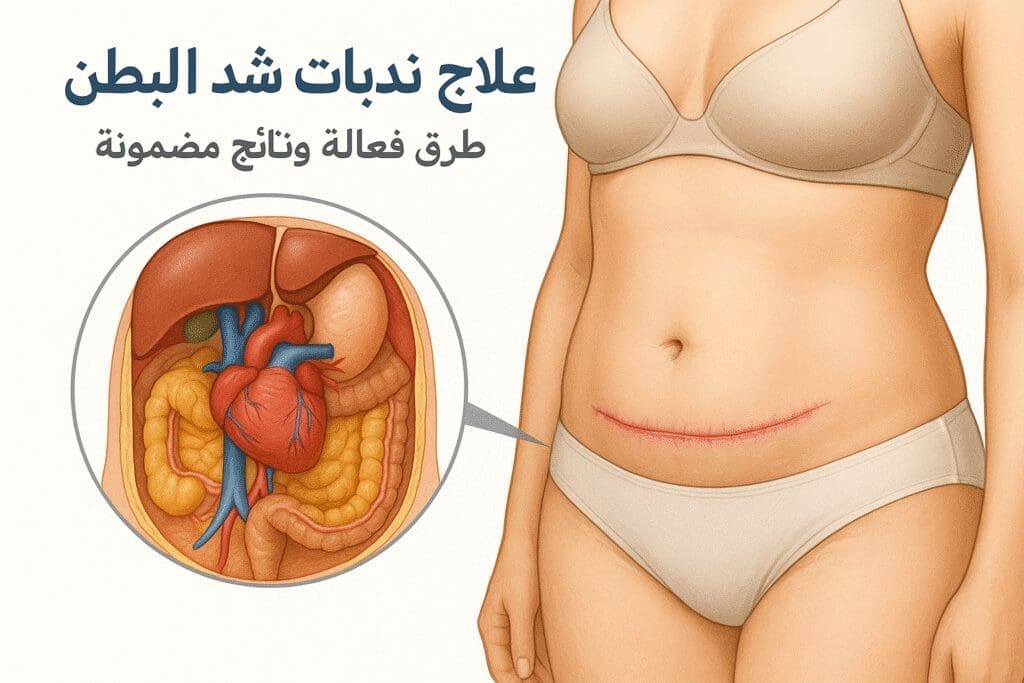

مقالات طبية من مساهمات الأطباء